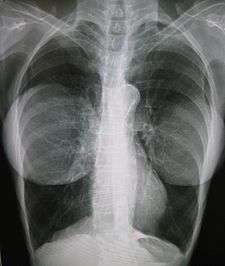

Implants and mammography

The presence of radiologically opaque breast implants (either saline or silicone) might interfere with the radiographic sensitivity of the mammograph, that is, the image might not show any tumor(s) present. In which case, anEklund view mammogram is required to ascertain either the presence or the absence of a cancerous tumor, wherein the breast implant is manually displaced against the chest wall and the breast is pulled forward, so that the mammograph can visualize a greater volume of the internal tissues; Nonetheless, approximately one-third of the breast tissue remains inadequately visualized, resulting in an increased incidence of mammograms with false-negative results.[86]